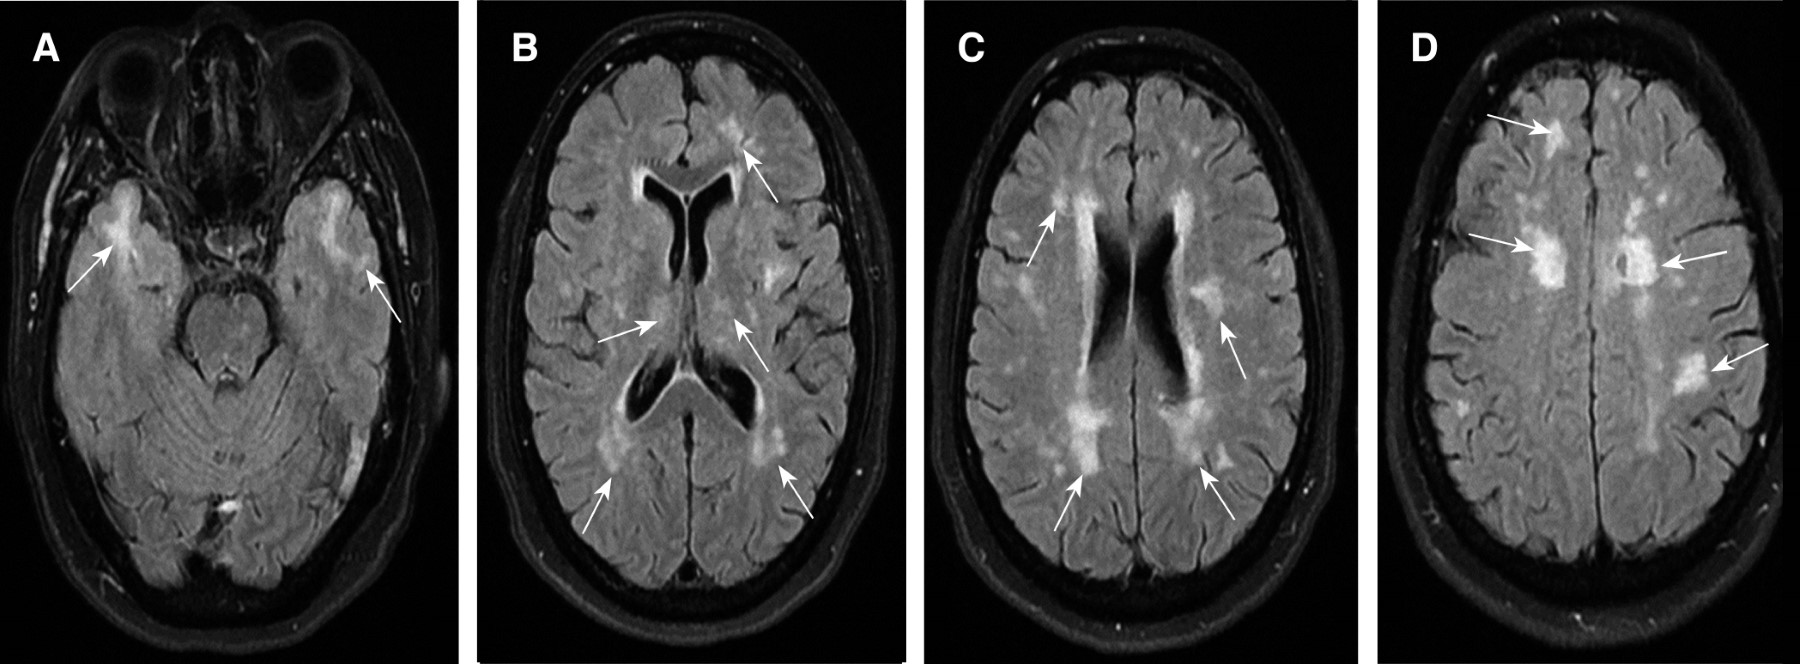

A los 46 años presentó súbitamente aumento de la debilidad hemicorporal derecha y disartria, se realizó IRM cerebral encontrando en secuencia T2 lesiones hiperintensas en sustancia blanca a nivel del bulbo, puente y pedúnculo cerebeloso inferior izquierdo (Figura 1) y en secuencia fluid-attenuated inversion recovery (FLAIR) lesiones hiperintensas en sustancia blanca superficial y profunda en ambos polos temporales, parietal y frontal bilateral, periventriculares, periatriales, adyacentes a la ínsula y en cuerpo calloso (Figura 2), sugestivos de EVC isquémico en territorio de la arteria cerebral media izquierda en su segmento M2. Los exámenes de laboratorio y gabinete, incluyendo proteína C y S, antitrombina III, factor V de Leyden, angiotomografía de troncos supraaórticos, electrocardiograma, estudio Holter, ecocardiograma, todos dentro de la normalidad. Se realizó estudio genético, el cual reportó mutación del gen NOTCH3 c.544C>T (pL151P). Se inició tratamiento de profilaxis secundaria con atorvastatina y ácido acetilsalicílico e ingresó al programa de rehabilitación física.

En cuanto a las lesiones subcorticales, las características radiológicas de las lesiones desmielinizantes por resonancia magnética (RM) son: lesiones en secuencia T1 hipoisointensas, FLAIR hiperintensas y con reforzamiento en anillo abierto con medio de contraste de localización periventricular, cortical o yuxtacortical, regiones cerebrales infratentoriales y médula espinal.16 En CADASIL se encuentran clásicamente amplias lesiones subcorticales confluentes en secuencia T2 prominentemente de los polos temporales anteriores (86%), cápsula externa (93%), además de núcleos de la base, tálamo y puente con un ahorro relativo de la sustancia blanca occipital, orbitofrontal, fibras en U subcorticales y corteza.19 La paciente en los estudios de RM en la secuencia FLAIR presenta lesiones hiperintensas en ambos polos temporales anteriores y cápsula externa sin afección de las fibras en U subcorticales y corteza, lo que concuerda con la descripción radiológica de CADASIL, además a nivel periventricular existe afectación de la sustancia blanca adyacente, lo cual no cumple con las recomendaciones para la prevención de errores diagnósticos de EM cuando se utilizan los criterios de McDonald 2017.16

Figura 2